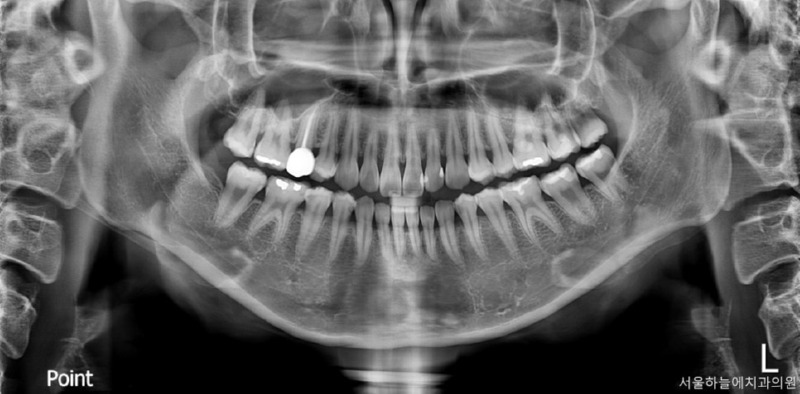

- 정밀 진단

파노라마 X-ray 촬영을 기본으로 하며,

필요 시 CT 촬영을 통해

충치 범위와 주변 구조를 정확히 파악합니다.